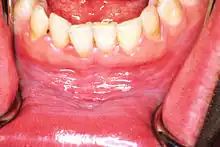

![]() | |

| Leukoplakia on the inside of the cheek | |

Oral leukoplakia is a potentially malignant disorder affecting the oral mucosa. It is defined as "essentially an oral mucosal white/gray lesion that cannot be considered as any other definable lesion." Oral leukoplakia is a gray patch or plaque that develops in the oral cavity and is strongly associated with smoking.[8] Leukoplakia is a firmly attached white patch on a mucous membrane which is associated with increased risk of cancer.[4][5] The edges of the lesion are typically abrupt and the lesion changes with time.[4][6] Advanced forms may develop red patches.[6] There are generally no other symptoms.[9] It usually occurs within the mouth, although sometimes mucosa in other parts of the gastrointestinal tract, urinary tract, or genitals may be affected.[10][11][12]

Homogeneous leukoplakia (also termed "thick leukoplakia")[2] is usually well defined white patch of uniform, flat appearance and texture, although there may be superficial irregularities.[2][9] Homogeneous leukoplakia is usually slightly elevated compared to surrounding mucosa, and often has a fissured, wrinkled or corrugated surface texture,[2] with the texture generally consistent throughout the whole lesion. This term has no implications on the size of the lesion, which may be localized or extensive.[2] When homogeneous leukoplakia is palpated, it may feel leathery, dry, or like cracked mud.[2]

Most cases of leukoplakia cause no symptoms,[9] but infrequently there may be discomfort or pain.[2] The exact appearance of the lesion is variable. Leukoplakia may be white, whitish yellow or grey.[29] The size can range from a small area to much larger lesions.[29] The most common sites affected are the buccal mucosa, the labial mucosa and the alveolar mucosa,[30] although any mucosal surface in the mouth may be involved.[2] The clinical appearance, including the surface texture and color, may be homogeneous or non-homogeneous (see: classification). Some signs are generally associated with a higher risk of cancerous changes (see: prognosis).